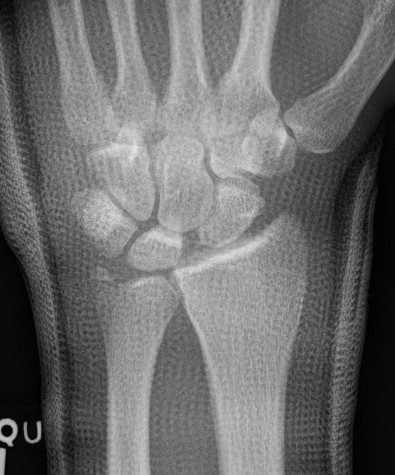

Dorsal radiocarpal dislocation with radial styloid fracture

Radial styloid + dorsal rim fractures